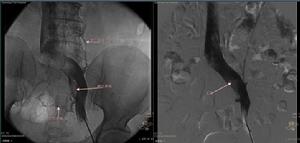

根據5例彩色超聲檢查均有肝靜脈狹窄閉塞,有2例伴肝段下腔靜脈狹窄。CT檢查2例,顯示肝尾葉代償性增大,增強掃描肝靜脈未顯示,奇靜脈和半奇靜脈擴張形成側支通道。MRI檢查1例顯示肝尾葉代償性增大,肝靜脈阻塞。下腔靜脈數字顯影(DSA)造影5例均未顯示肝靜脈,2例顯示肝靜脈開口“乳頭”征,2例肝段下腔靜脈狹窄,下腔靜脈側壓顯示狹窄兩端無明顯壓力差。經皮經肝穿刺肝靜脈造影顯示肝靜脈節段性阻塞2例,長0.5 cm~1.0 cm,膜性阻塞2例,4例均顯示肝靜脈擴張;1例顯示肝靜脈廣泛性閉塞,副肝靜脈細小並節段性閉塞。

1.4 方法

先經頸靜脈途徑穿刺,行下腔靜脈造影,然後經皮經肝穿刺肝靜脈造影。肝靜脈膜性閉塞的2例,用硬質導管導絲順行開通肝靜脈後,建立經皮經肝肝靜脈頸靜脈導絲軌道,用0.5 cm~1.2 cm球囊行肝靜脈擴張成形。肝靜脈節段性狹窄閉塞的開通,用RUPS100肝穿裝置,在B超引導下經頸靜脈途徑,穿刺肝段下腔靜脈,建立經皮經肝肝靜脈頸靜脈導絲軌道,然後經頸靜脈途徑用0.5 cm~1.2 cm球囊進行擴張成形,或植入血管內支架。術後抗凝治療:肝素4 000 IU/d,靜脈注射1周后改口服阿司匹林和潘生丁,2個月後複查彩色超聲,了解肝靜脈通暢情況。

根據5例肝靜脈型BCS,2例節段性阻塞段長為0.5 cm~1.0 cm,1例單純球囊擴張術(PTA)處理,1例PTA後放入血管內支架;2例膜阻塞均單純PTA。另1例肝靜脈廣泛性阻塞者,顯示副肝靜脈細小,並節段性阻塞,試用破膜針直接穿刺開通失敗,未行TIPSS。成功的4例,術後1 d~15 d患者症狀和體徵明顯好轉和消失。隨訪6個月~3 a,肝臟縮小,彩超複查,3例肝靜脈通暢。1例膜性閉塞者於PTA後10個月後發生再狹窄,再次PTA後6個月再狹窄,植入血管內支架,未再發生狹窄。